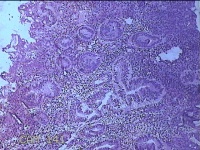

子宫腔赘生物

性别

女

年龄

33岁

临床诊断

子宫内膜息肉?子宫异常出血

一般病史

阴道流血12天。

标本名称

大体所见

灰白粉红色不规则肿物1.5x1.3x0.2cm一堆,表面糜烂。

图1